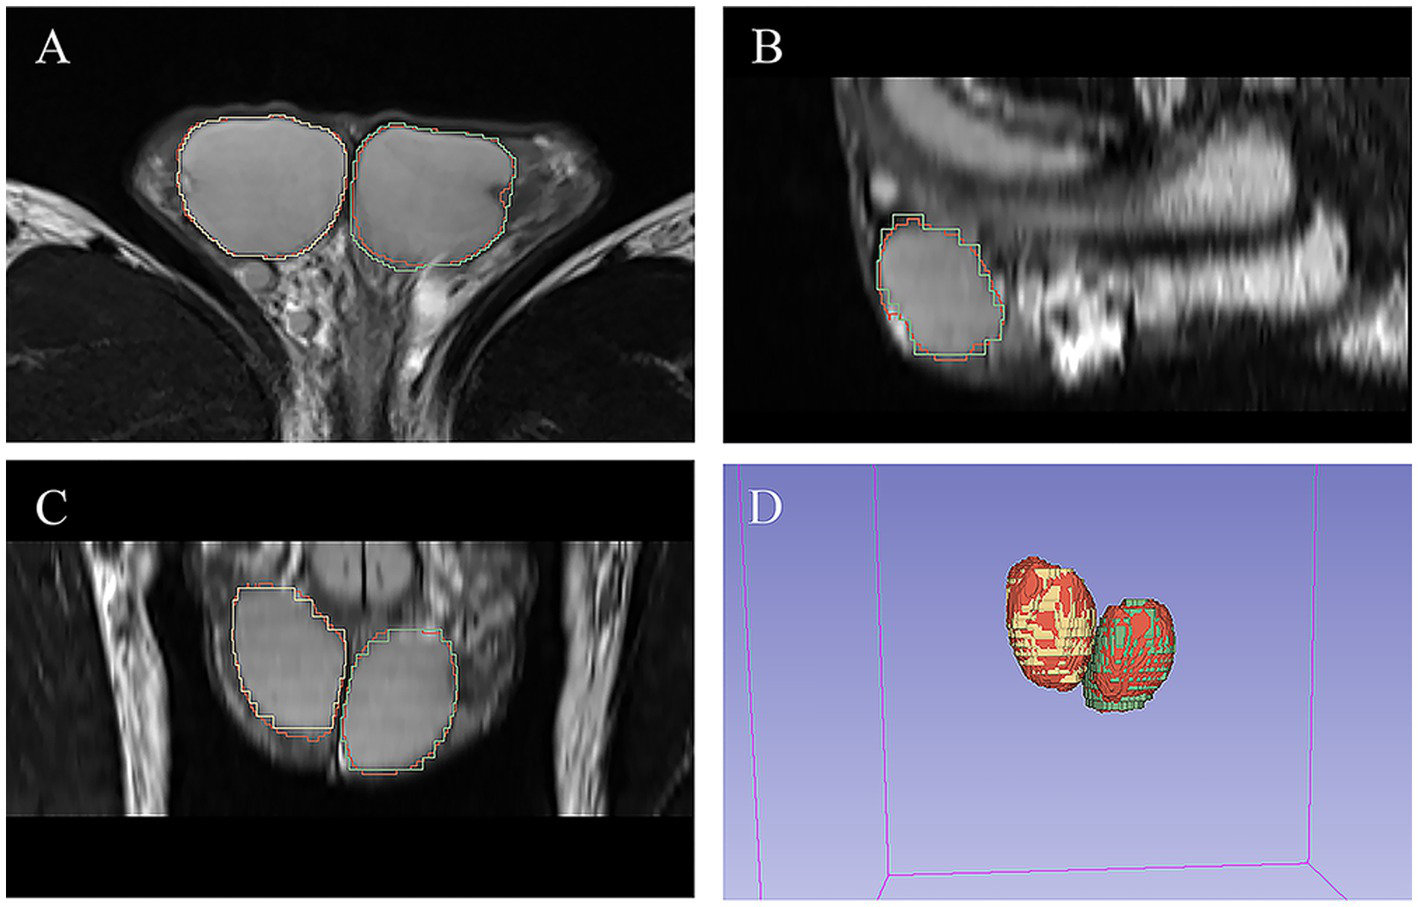

As shown in Table 3, there was excellent similarity between the automatic and manual segmentations, with a mean Dice score of 0.922 ± 0.02 (0.921 ± 0.026 for the left testis and 0.926 ± 0.034 for the right testis) in the validation cohort and a mean Dice score of 0.931 ± 0.018 (0.931 ± 0.019 for the left testis and 0.932 ± 0.022 for the right testis) in the testing cohort. Linear regression analysis indicated a strong positive correlation (R2 ranging from 0.974 to 0.987, p < 0.001 for the validation cohort; R2 ranging from 0.936 to 0.973, p < 0.001 for the testing cohort) between the manual TV and automated TV (Figure 2, Supplementary Figure S1). For TTV, the bias (mean) and precision (SD) of the automated measurements were 0.838 and 0.991 in the validation cohort and 0.815 and 0.824 in the testing cohort. For LTV, the bias and precision of the automated measurements were 0.209 and 0.665 in the validation cohort and 0.303 and 0.664 in the testing cohort. For RTV, the bias and precision of the automated measurements were 0.630 and 0.728 in the validation cohort and 0.511 and 0.824 in the testing cohort. In terms of volume error, the actual volume differences between manual measurements and automated measurements were 0.209 ± 0.665 for LTV, 0.630 ± 0.728 for RTV, and 0.838 ± 0.991 for TTV in the validation cohort. In the testing cohort, the percentage volume differences between manual measurements and automated measurements were 0.303 ± 0.664 for LTV, 0.511 ± 0.444 for RTV, and 0.815 ± 0.824 for TTV. The percentage volume differences between manual measurements and automated measurements were 2.192 ± 6.129% for LTV, 4.654 ± 7.355% for RTV, and 3.711 ± 4.983% for TTV in the validation cohort. In the testing cohort, the percentage volume differences between manual measurements and automated measurements were 2.621 ± 5.580% for LTV, 3.909 ± 3.856% for RTV, and 3.266 ± 3.668% for TTV. Figure 3 illustrates an example of manual segmentation alongside the corresponding automated segmentation generated by the deep learning model.

Figure 3

Example of manual and automated segmentation of the testes. (A) Axial view. (B) sagittal view. (C) Coronal view. (D) 3D volume. The manual mask generated by experts for left testis is shown in blue, the manual mask for right testis is shown in green, and the automatically generated mask is shown in red.